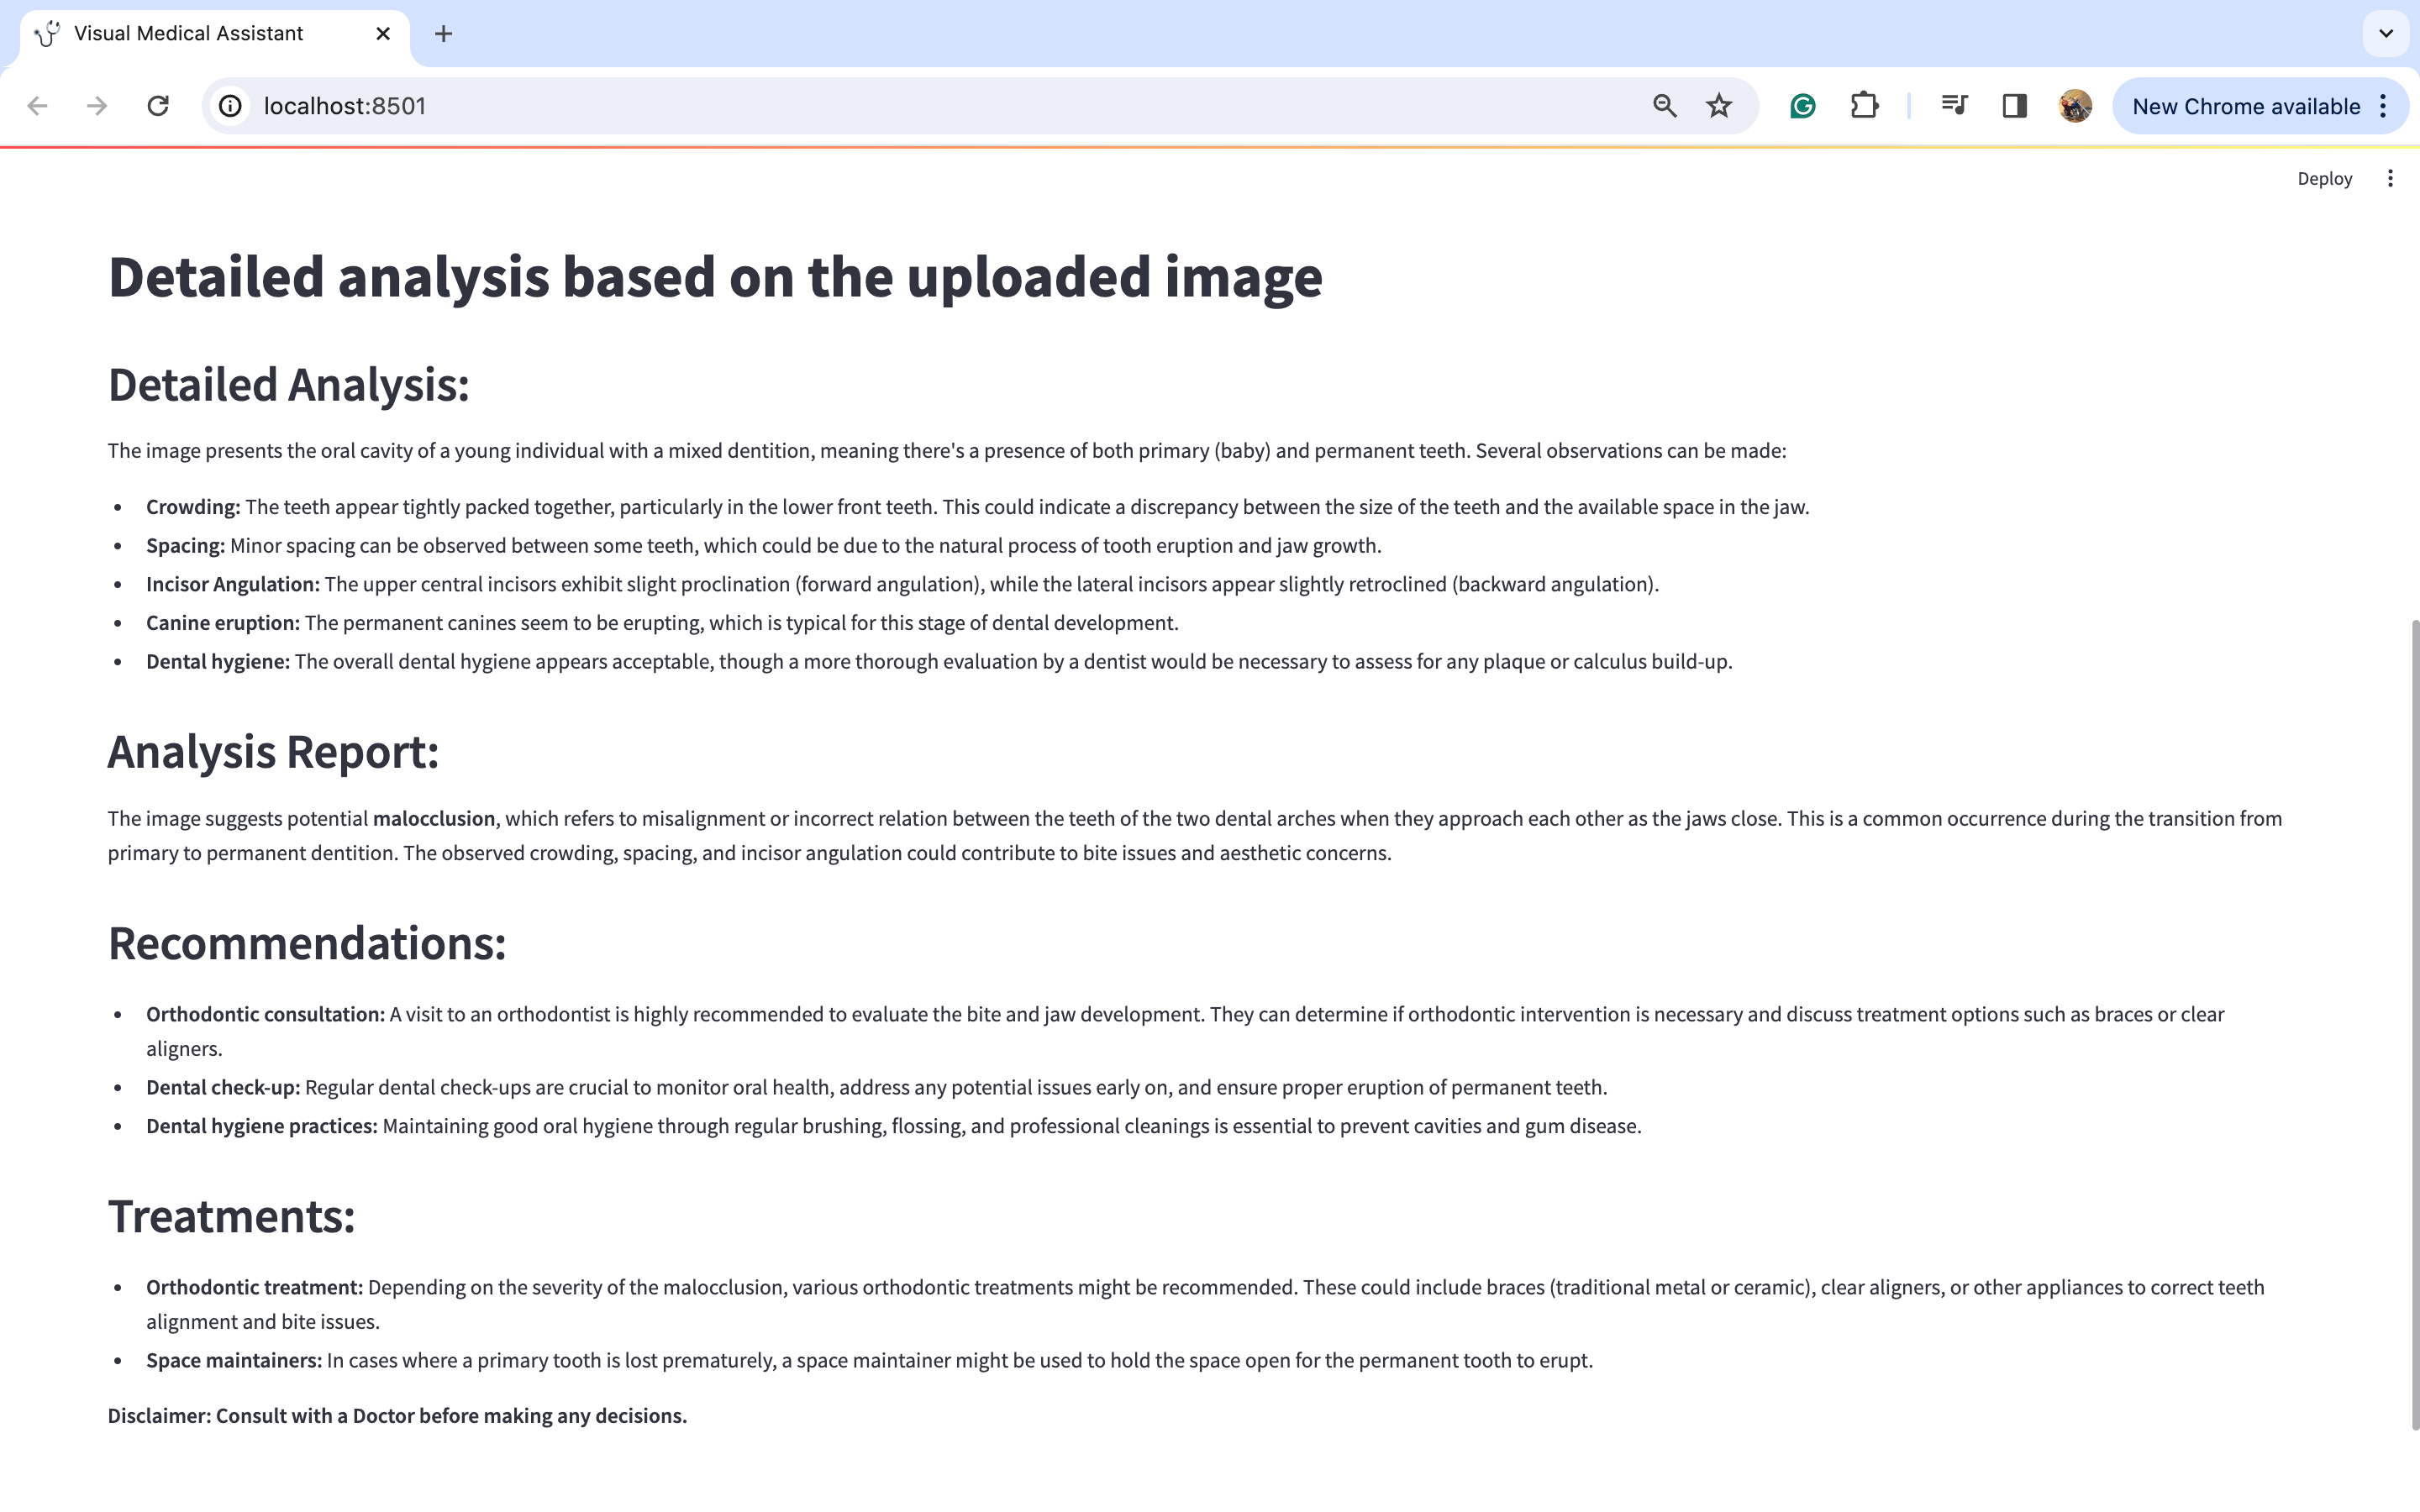

图片上传后,点击“生成分析”按钮。您将在下方看到详细的分析结果:

我知道图片可能有点难以阅读,所以我将分享每个标题的放大图片,以便更容易理解。

图片1:

图片2:

图片3:

通过仔细观察图片,我们可以对潜在的医疗诊断进行深入分析。此外,考虑到这与牙齿问题有关,建议的行动方案是咨询正畸医生并进行一些牙齿X光检查。此外,在这种情况下,佩戴牙套和保持器等多种治疗选择似乎是明智的选择。